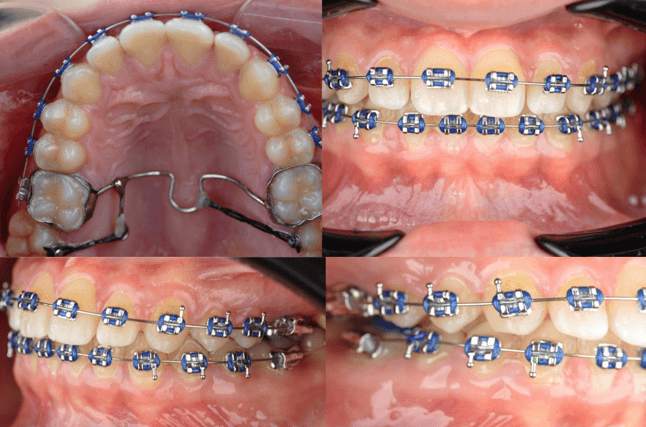

25 de octubre de 2024 (figura 10)

Se realizó ajuste clínico en ambas arcadas, manteniéndose los arcos. Se cementó nuevamente el tubo del órgano dentario 36 el cual se había despegado.

Figura 10. Ajuste.